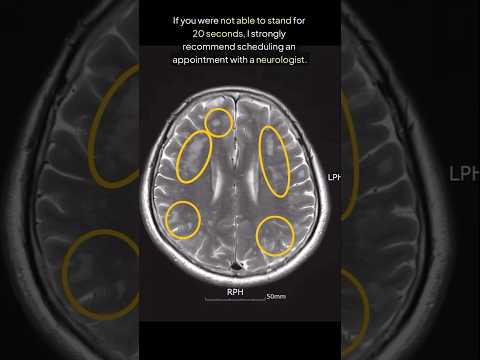

DO NOT Fail This Brain Test (For Early Dementia)